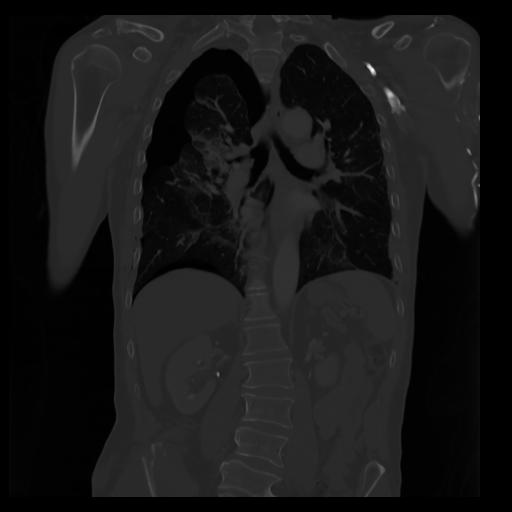

29 CUERPO,CE,Coronal,3.000,CUERPO,Coronal,